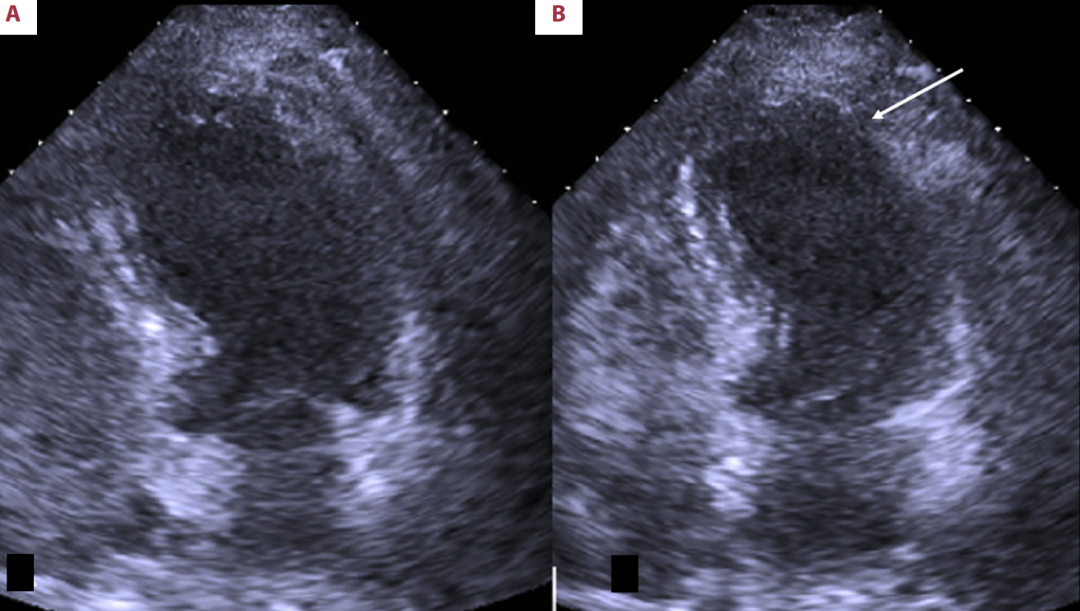

第二次(2016年)发作(图2):当时显示心尖部和中远段前侧壁运动消失(无运动),LVEF50%。这是更接近经典的心尖部受累模式。

图2

2016年经胸超声心动图显示的心室四腔视图;舒张期(A)与收缩期(B)。B图中的箭头指示了收缩期间心室中段前外侧壁及心尖区域的运动缺失情况。